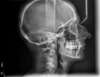

Encombrements traités par gouttières

G-Intermédiaire 3